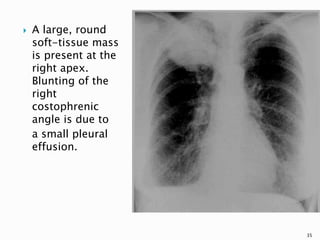

 A large, round

soft-tissue mass

is present at the

right apex.

Blunting of the

right

costophrenic

angle is due to

a small pleural

effusion.